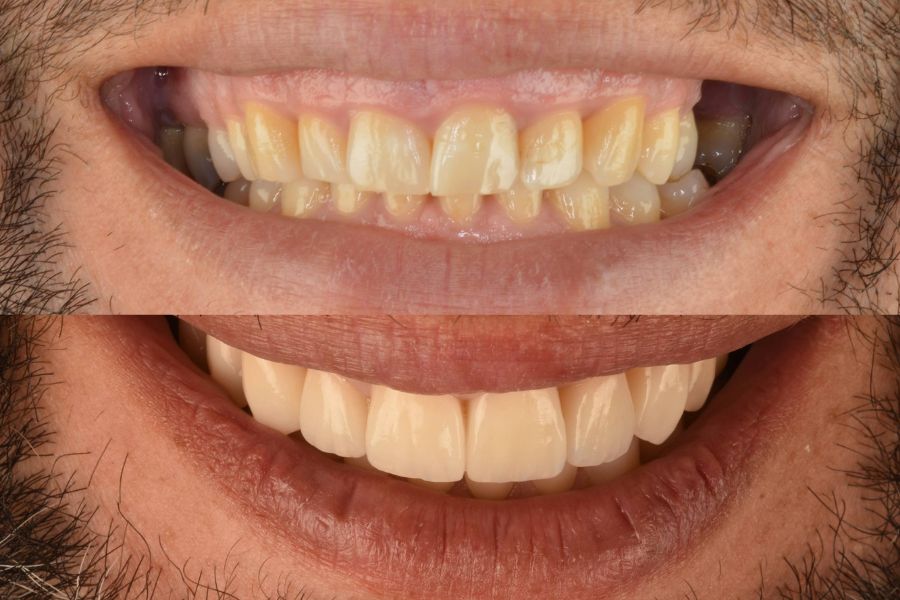

Antes y después del tratamiento

Las últimas imágenes muestran el resultado final del tratamiento. El paciente logró una sonrisa equilibrada, con proporciones naturales y una mordida estable.

La mejora no fue solo estética, también recuperó la función masticatoria y una gran sensación de confort al cerrar y abrir la boca.